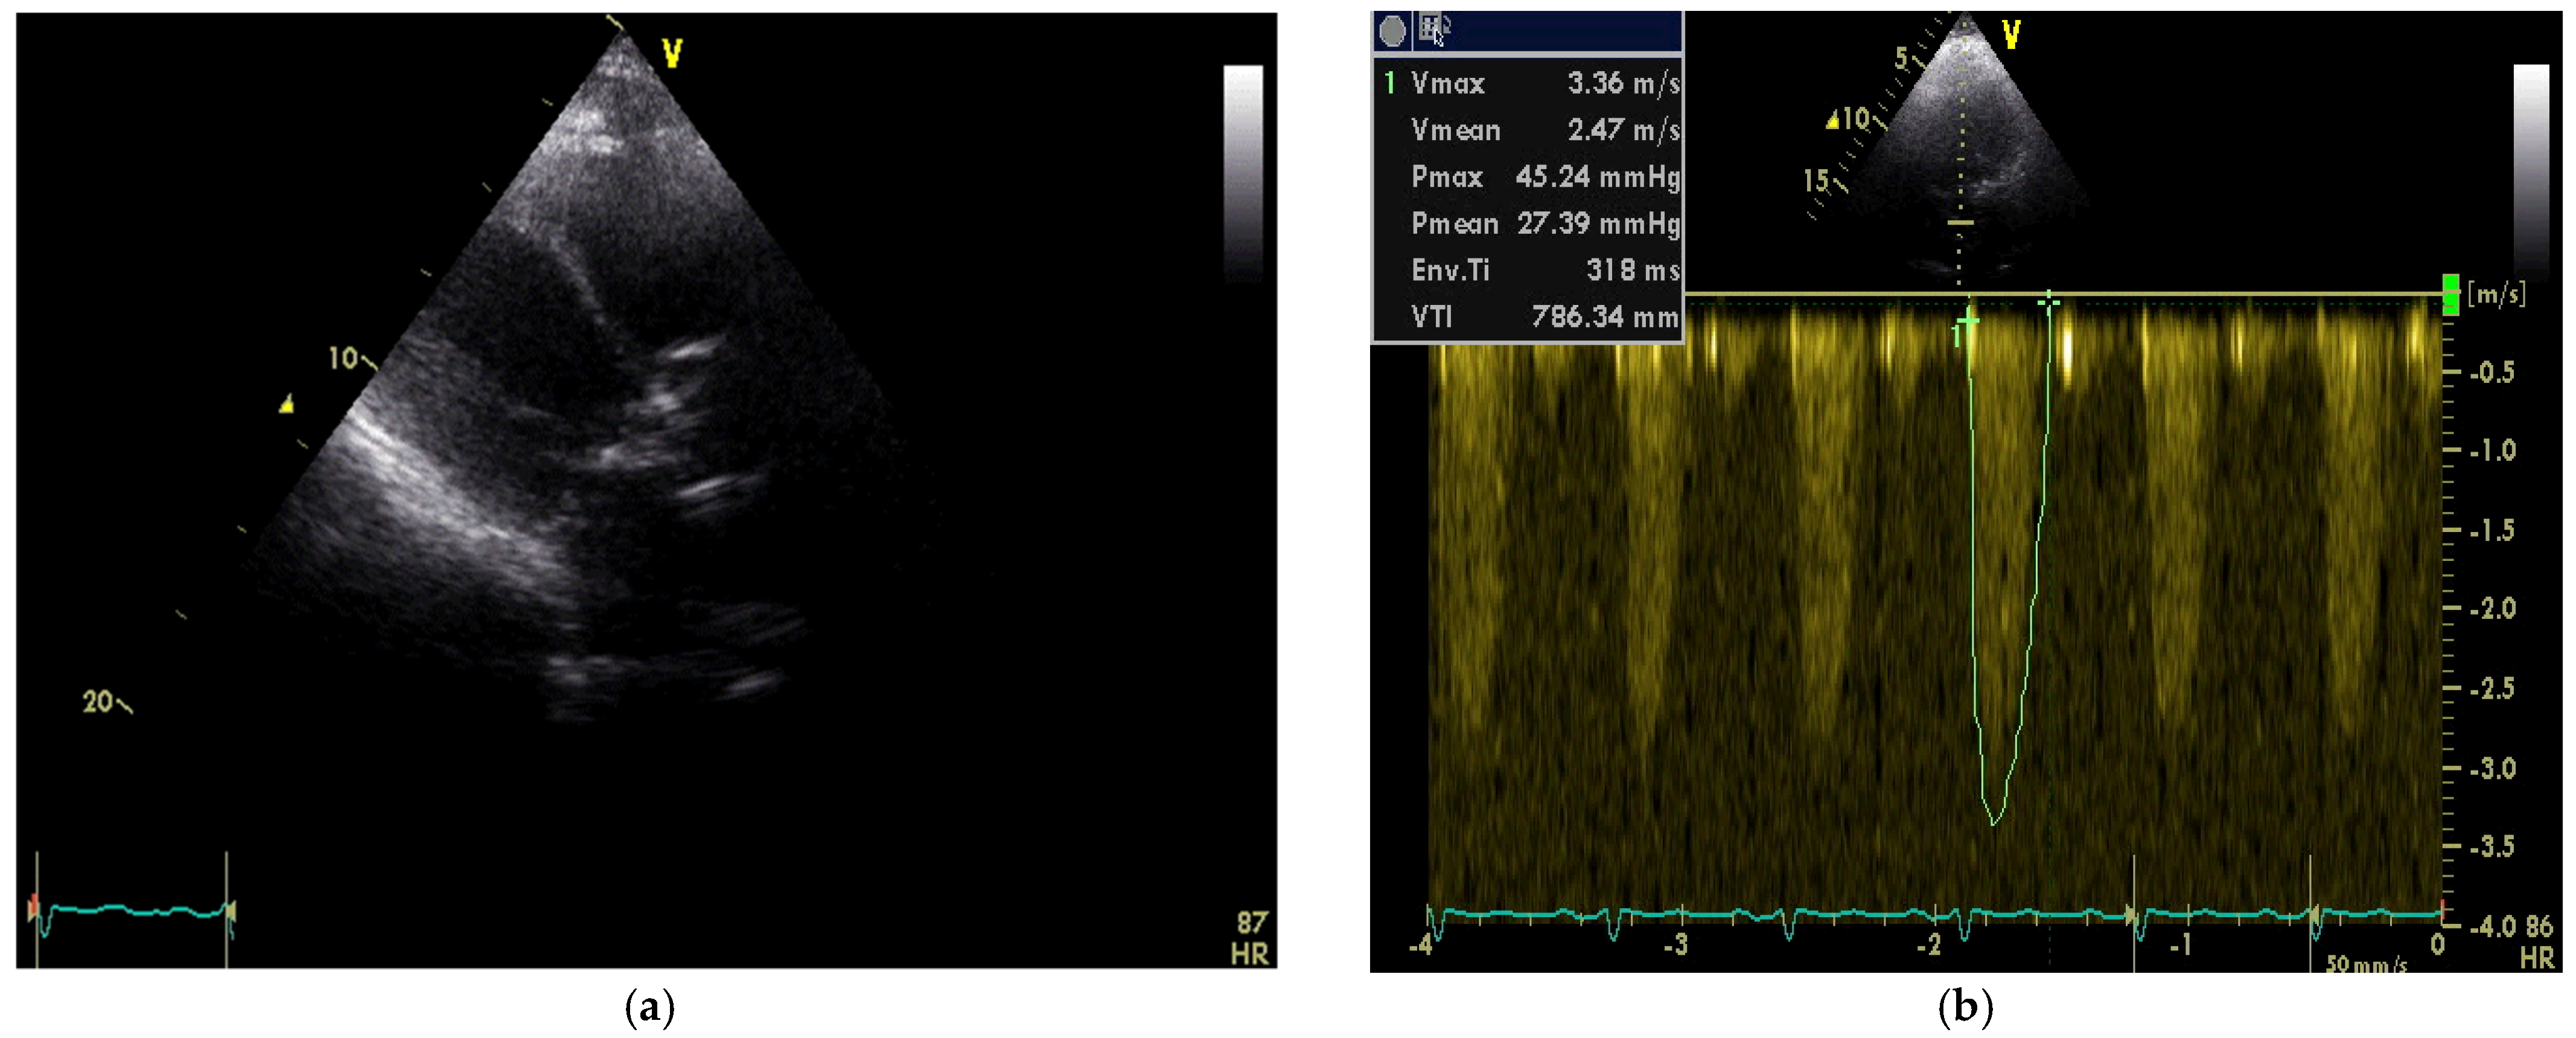

Transthoracic echocardiography (TTE) demonstrated fibrocalcinosis of aortic root, aortic valve annulus, aortic valve cusps (Figure 2a) and moderate to severe aortic stenosis (Vmax 3.36 m/s, Gmean27 mmHg) (Figure 2b), decreased left ventricular (LV) systolic function (ejection fraction 35%), thickened, fibrotic pericardium. In the presence of right ventricular (RV) pressure overload, the interventricular septum shifted towards the LV.

Figure 2. (a) Transthoracic echocardiography demonstrated fibrocalcinosis of aortic root, aortic valve annulus, aortic valve cusps and pericardium; (b) Peak velocity through aortic valve 3.36 m/s, mean gradient through aortic valve—27.39 mmHg.